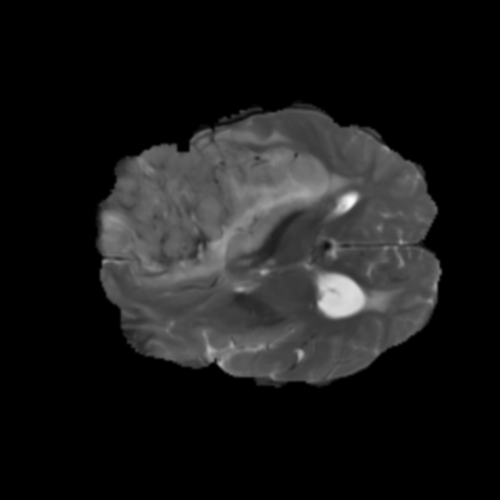

Ejemplos de Modalidades MRI

Visualización de las 4 modalidades de resonancia magnética y las segmentaciones de zonas tumorales utilizadas para entrenar el modelo

Glioma de Bajo Grado (LGG)

FLAIR LGG

FLAIR

T1ce LGG

T1ce

T2 LGG

T2

T1 LGG

T1

Núcleo LGG

Núcleo

Edema LGG

Edema

Realce LGG

Realce

Tumor Completo LGG

Tumor Completo

Núcleo Edema Realce